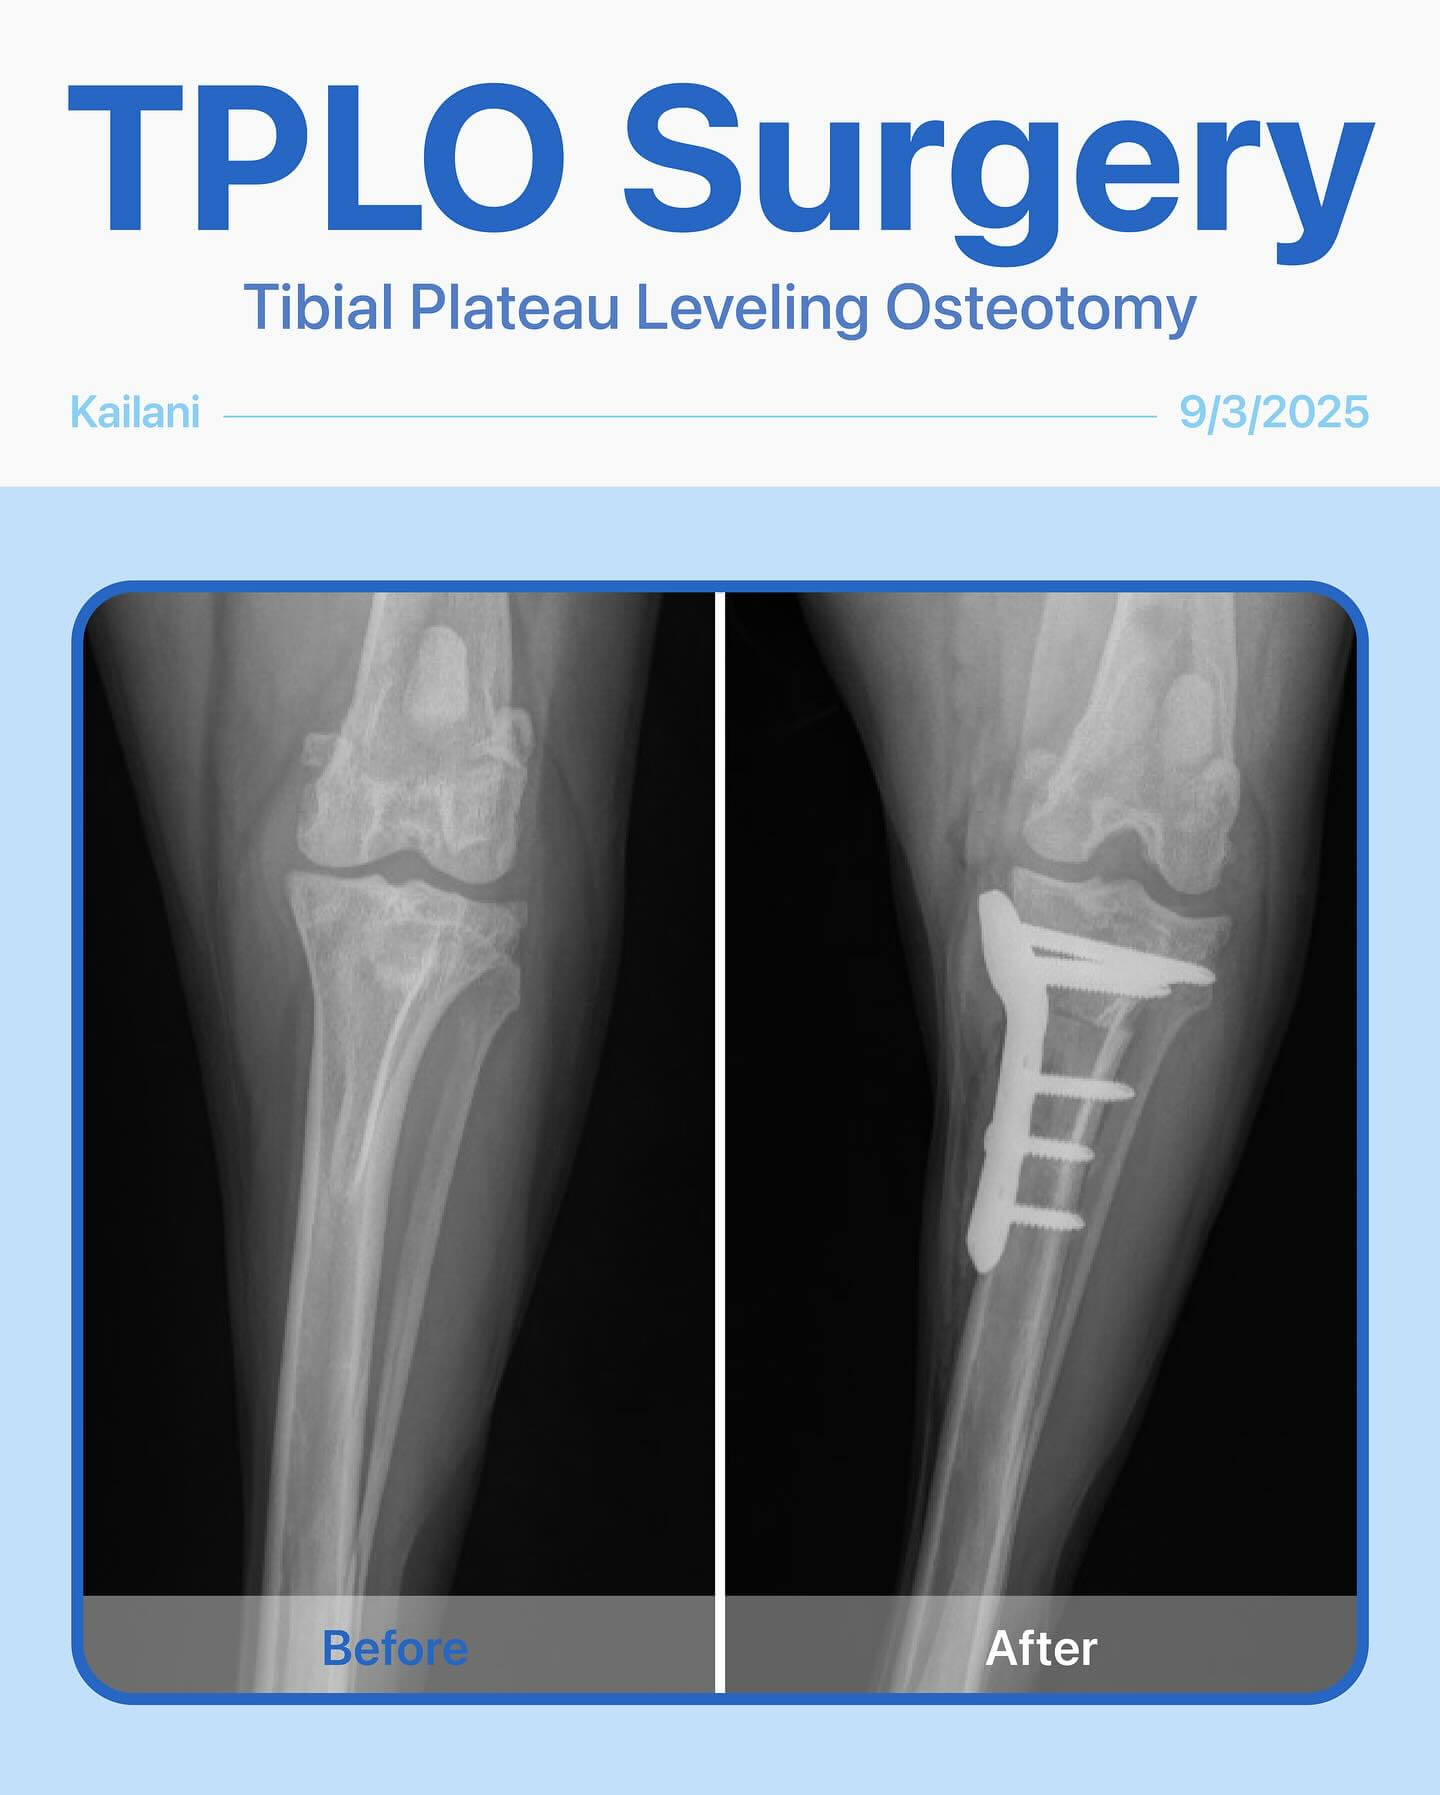

Meet Kailani, a 1-year-old Poodle mix who had been limping on her left back leg for the past 4 months. After a thorough exam and radiographs, we found she had a cranial cruciate ligament tear—a common injury that can make every step painful.

She needed TPLO surgery to restore stability and get back to her playful, happy self. Since both legs were affected, we decided to start with the left first to give her the best chance at a smooth recovery.